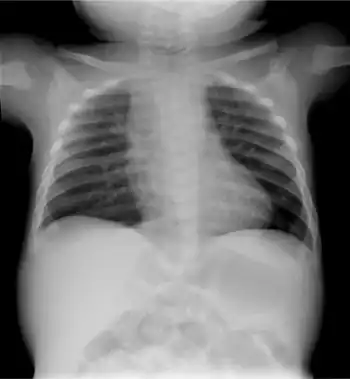

| Infant male with the brachytelephalangic type of chondrodysplasia punctata | |

Chondrodysplasia punctata is a clinically and genetically diverse group of rare diseases, first described by Erich Conradi (1882–1968), that share the features of stippled epiphyses and skeletal changes.[1]: 500 [2]: 549